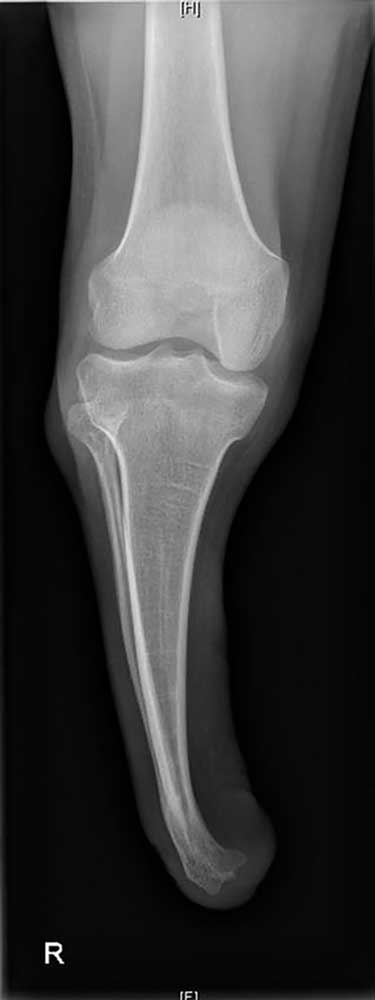

Es handelt sich um ein 9‑jähriges Mädchen, dem im Rahmen einer Streptokokkensepsis im Alter von 4 Jahren beidseitig die Unterschenkel amputiert wurden. Durch die frühe Amputation entstand eine sehr kurze Tibia, die sich im weiteren Verlauf jedoch nicht weiterentwickelte. Erfreulicherweise hat sich aber die Fibula durch die besondere Belastung und den „Prothesendruck“ der Tibia quasi unterstellt (Abb. 2). Somit ist nicht nur eine ausreichende Stumpflänge zur Prothesenversorgung, sondern auch eine ausreichende Stabilität gegeben, wodurch das Kniegelenk funktionell erhalten bleibt. Zwar müssen dabei aufgrund der sehr kurzen und eigentümlichen Hebelverhältnisse bestimmte Einschränkungen hinsichtlich der Kraftübertragung zwischen Stumpf und Schaft in Kauf genommen werden, und die Bettung des Stumpfes erfordert besondere Modelltechniken, die nicht analog zu einem klassischen Stumpf sind, aber es ergeben sich doch gute funktionelle Ergebnisse. Dennoch bedarf es einer engen Anbindung an das Versorgungsteam und einer engmaschigen Kontrolle der Patientin im weiteren Verlauf, um potenziell negativen Entwicklungen rechtzeitig begegnen zu können.